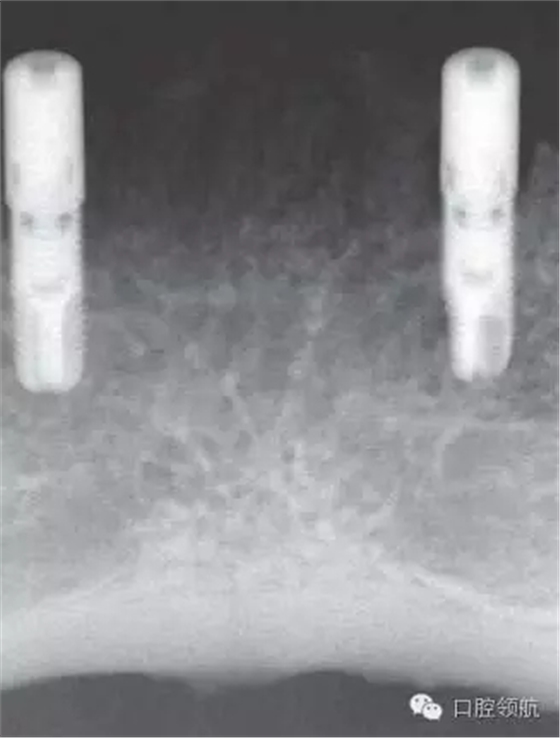

術(shù)后3個(gè)月,能夠看到種植體周圍有充足的角化齦(圖8、圖9)。

圖9 種植體植入3個(gè)月后曲面斷層影像。